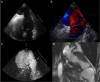

Unsuspected large left ventricular pseudoaneurysm: rapid bedside diagnosis by contrast-enhanced echocardiography